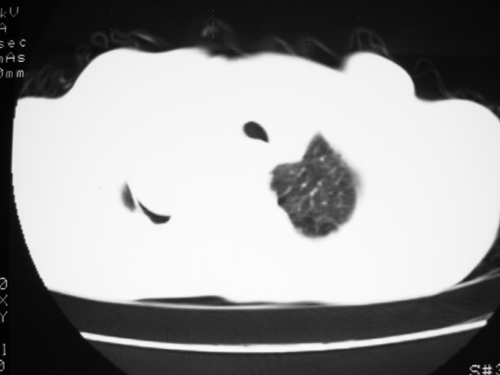

以下是引用yangyudong333在2008-4-29 5:46:00的发言:[br]1左上叶结节呈分叶状,边缘毛刺,考虑肺癌并纵隔淋巴结转移可能性大,结核待排,[br] [br]2右侧多发包裹性胸腔积液